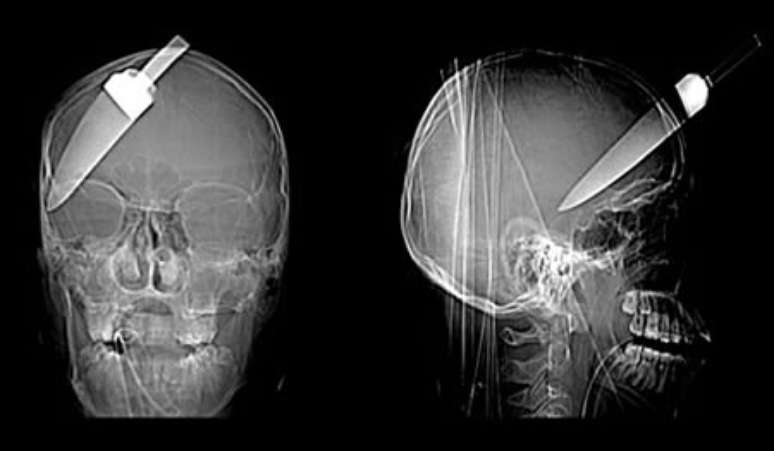

Um adolescente de 16 anos escapou da morte, após ter uma faca de 5 polegadas introduzida em sua cabeça. O jovem foi levado ao hospital com a faca ainda na cabeça